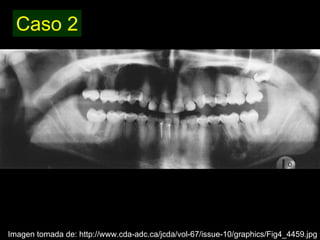

Dentinogénesis imperfecta es una condición genética que causa un disturbio en la formación de la dentina. Existen tres tipos principales. El tipo I se asocia con osteogénesis imperfecta. El tipo II solo afecta la dentina y causa dientes amarillos o grises con atrición. El tipo III es raro y se encuentra en un área aislada de Maryland, con exposiciones pulpares frecuentes. Todos los tipos muestran características radiográficas como obliteración de cámaras y conductos,